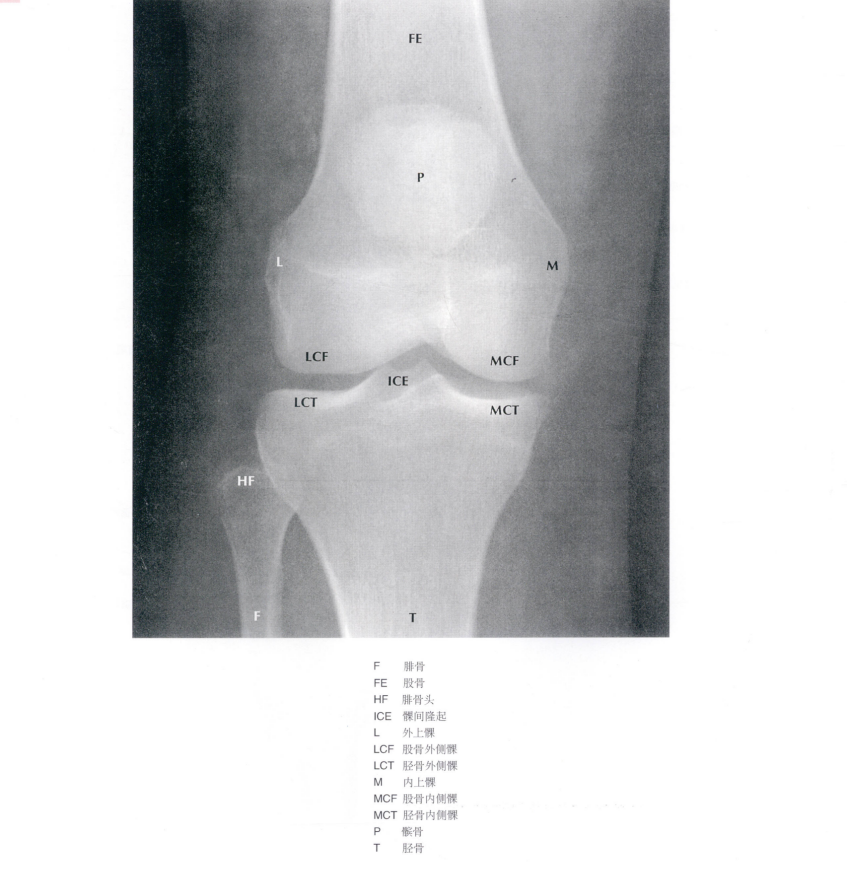

髕骨的解剖結(jié)構(gòu)

髕骨位于膝關(guān)節(jié)伸膝裝置的里面,解剖特征包括其正好位于關(guān)節(jié)的中部,有一個(gè)關(guān)節(jié)外面、

一個(gè)關(guān)節(jié)內(nèi)面和一個(gè)關(guān)節(jié)外下極。股直肌和股中間肌的止點(diǎn)經(jīng)過髕骨的上表面;股內(nèi)側(cè)肌和股外側(cè)肌經(jīng)過其兩側(cè)。

圖源:奈特人體解剖彩色圖譜

髕韌帶起自髕骨下極止于脛骨結(jié)節(jié)。髕骨的內(nèi)關(guān)節(jié)面有人體最厚的軟骨層約有5mm,反映出髕股關(guān)節(jié)承受非常高的負(fù)荷,這正是容易發(fā)生髕骨軟化及關(guān)節(jié)退變的原因。它集中股四頭肌各方向的牽引力,再通過髕韌帶止于脛骨結(jié)節(jié),有效完成股四頭肌的伸膝動(dòng)作。